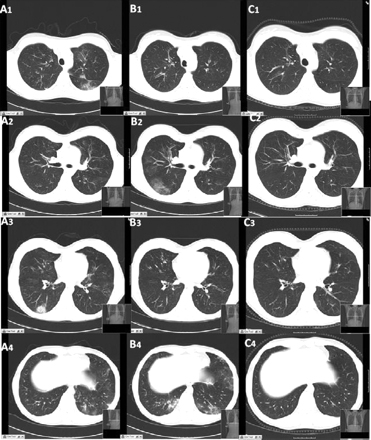

Tomografia computadorizada (TC) do tórax obtida (A) durante a exacerbação dos sintomas, revelando infiltrados pulmonares no lobo inferior direito (A3) e no lobo inferior esquerdo (A4). Uma reavaliação feita 15 dias depois (B) revelou a natureza migratória das lesões, com o desaparecimento completo dos infiltrados descritos anteriormente e a presença de novas áreas com opacidade em vidro fosco dentro do lobo inferior direito (B2) e do segmento lingular esquerdo e do lobo inferior esquerdo (B4). (C) Seis meses após o tratamento, todas as lesões pulmonares descritas estavam completamente curadas

BMJ Case Reports 2009; doi:10.1136/bcr.04.2009.1731. Copyright © 2011 by the BMJ Publishing Group Ltd